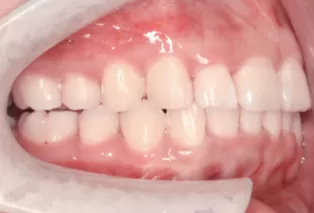

Female, 25 years old. Chief complaint: protruding and misaligned teeth, requiring orthodontic treatment.

Intraoral photos

Before Treatment